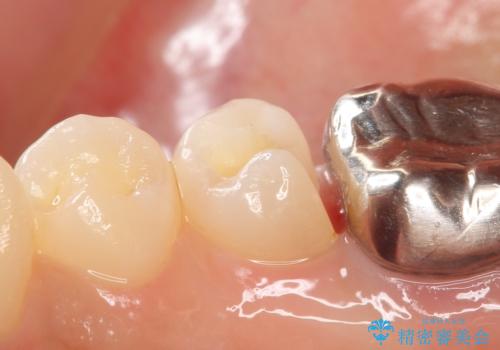

- 右下5番目の歯がしみるといらっしゃった方の症例です。

銀歯及び虫歯を除去し、適合に優れたPGA(ゴールド)インレーにて修復を行いました。